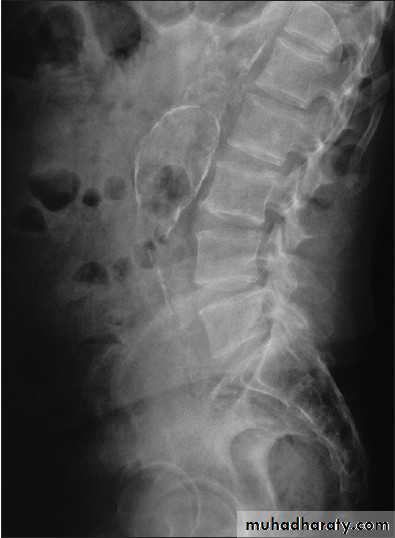

Abdominal calcifications

3. Vascular calcification: e.g. aortic aneurysm which best assessed on lateral film

11. Pancreatic calcification: occur in chronic pancreatitis & diagnosed from it's position